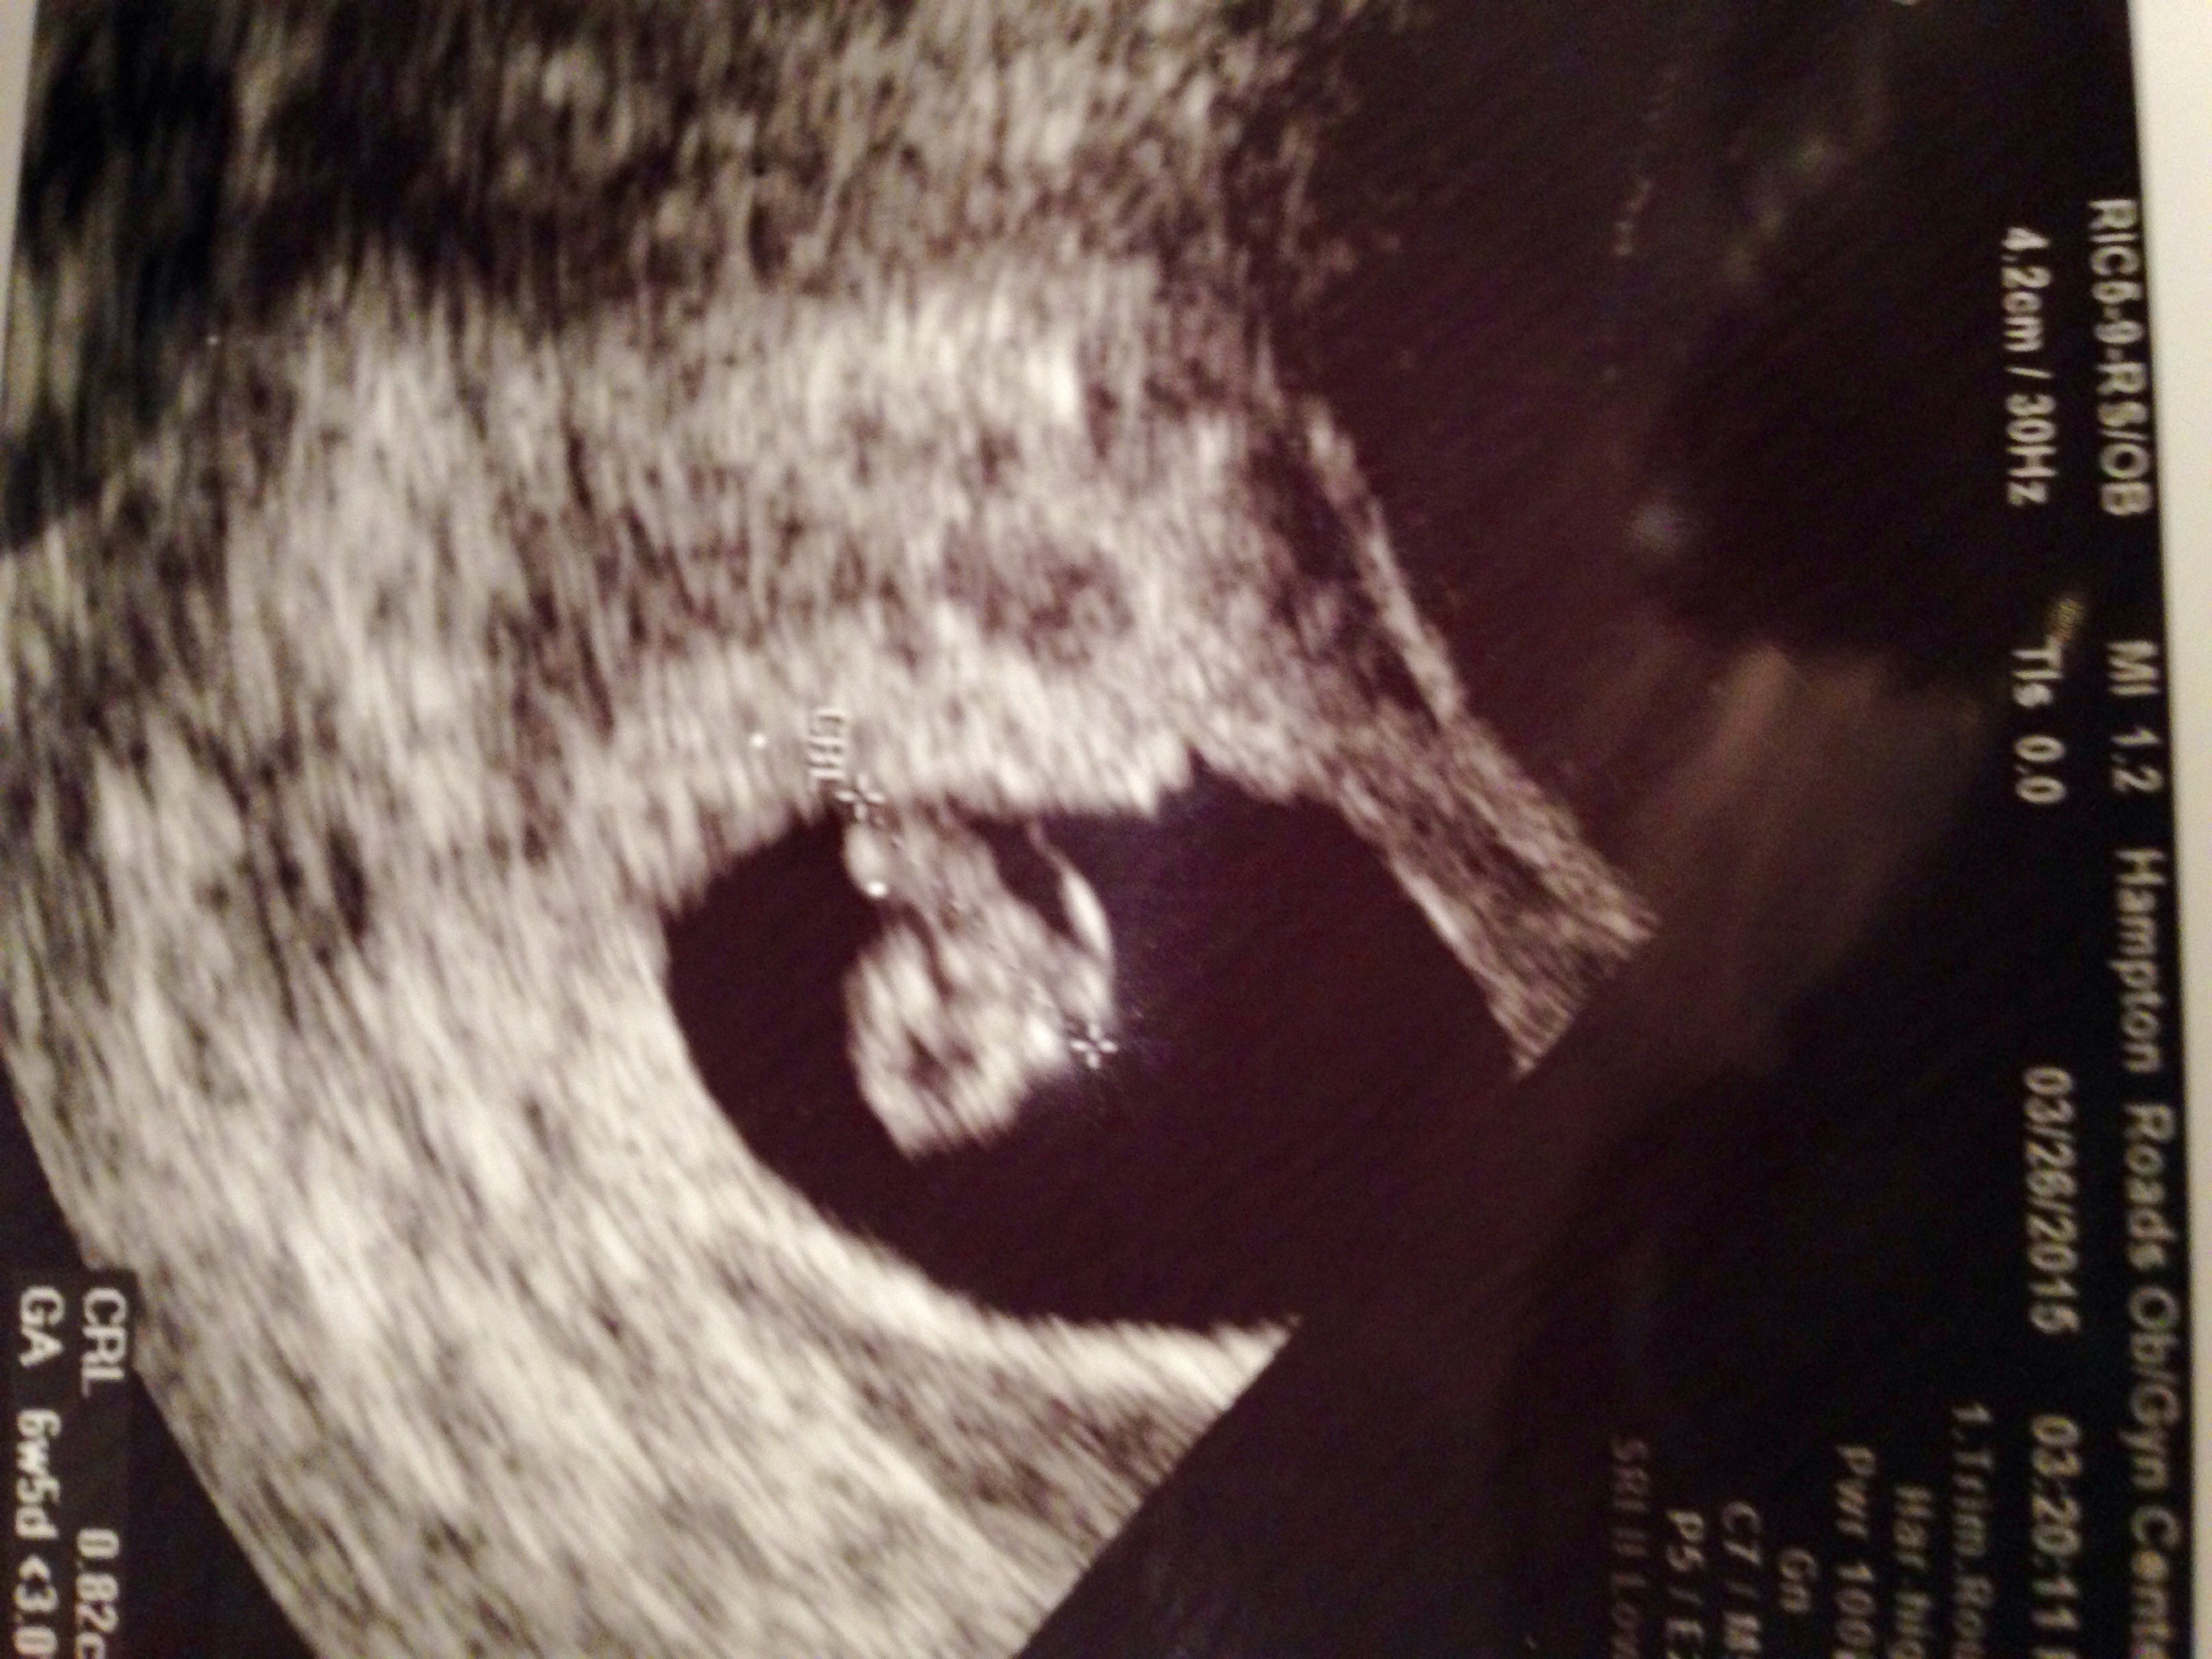

EDD 11-9 currently 7w4d measuring 6w6d. Not understanding the Ramzi method at all! Lol any help would be great! Both gender charts say boy!

*TransV U/S

+ the second picture is sideways but it looks like the blueberry switched sides in the picture...?